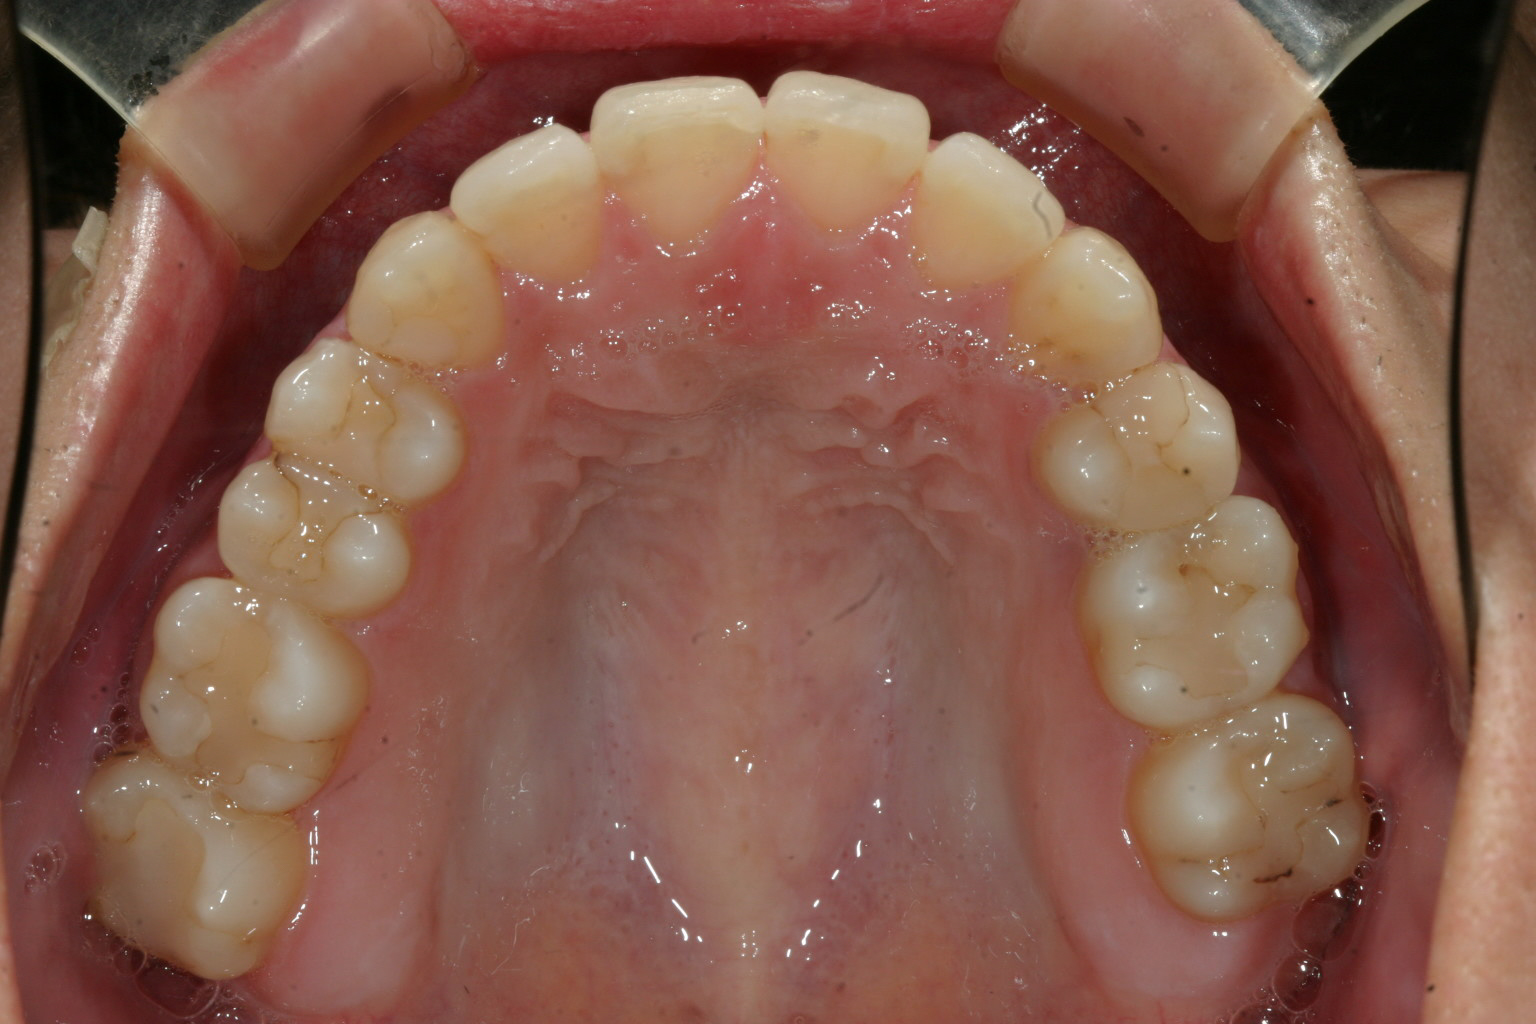

上顎には少しの叢生が有るだけです。

上顎はアーチを広げて叢生を綺麗に取りました。